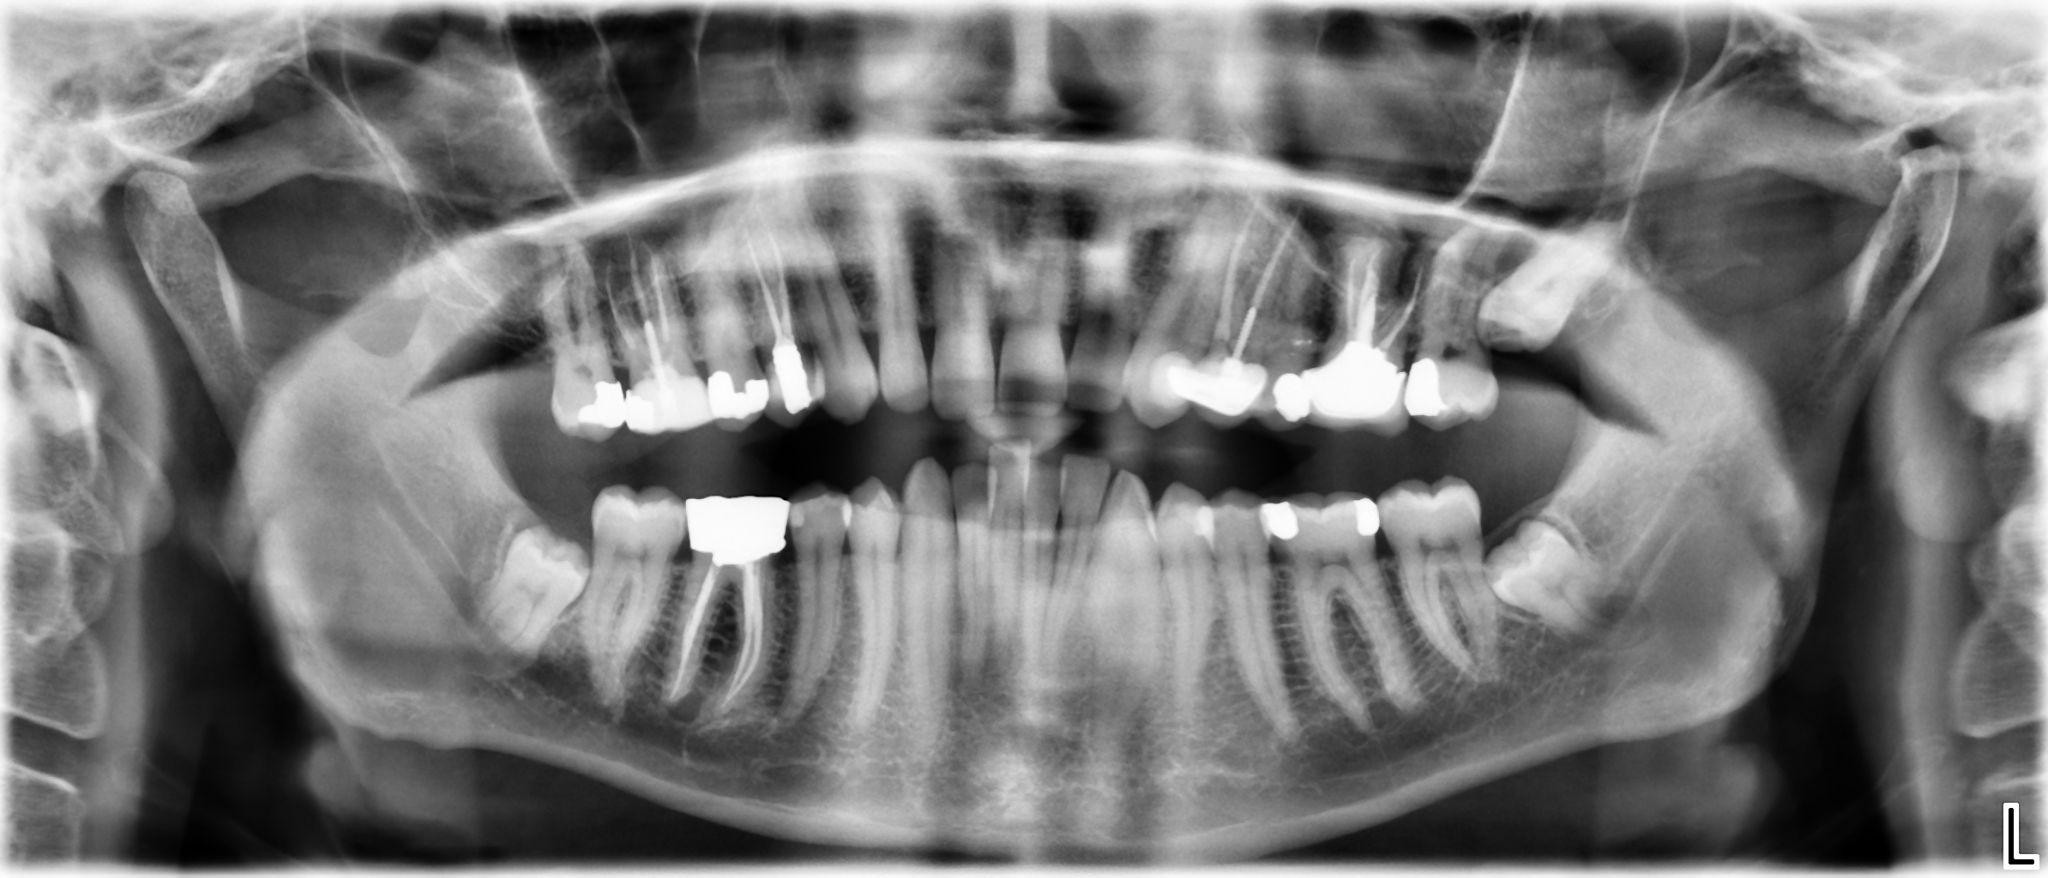

1. What options can be selected for the first quadrant of this panoramic X ray?

2. What options can be selected for the second quadrant of this panoramic X ray?

3. What options can be selected for the third quadrant of this panoramic X ray?

4. What options can be selected for the forth quadrant of this panoramic X ray?